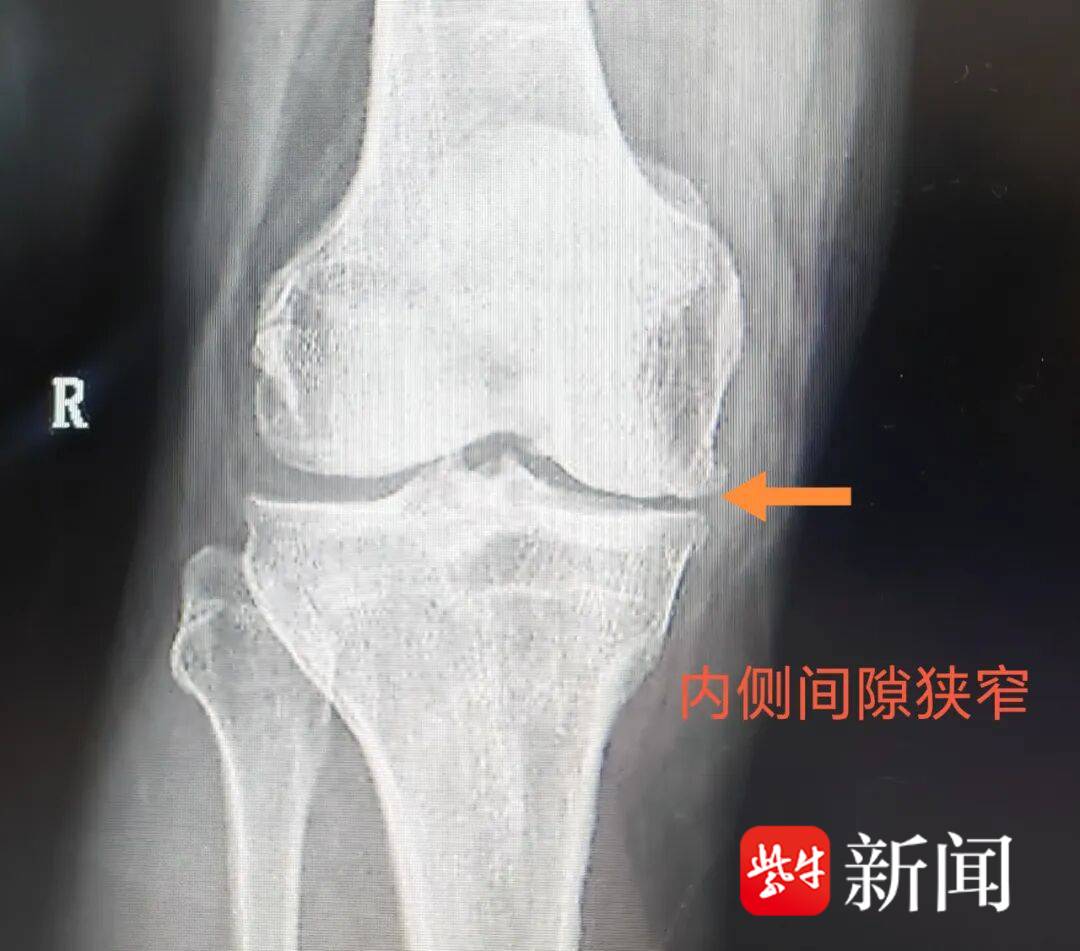

周荣主任带领团队为余大爷行置换术,手术很成功。

![]()

术后影像资料